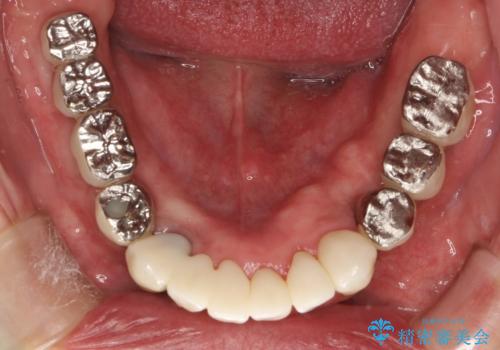

費用・時間は多大にかかりましたが、今後しっかりと咬んで生活することができるでしょう。

かみ合わせの力が非常に強く、夜間の歯ぎしり・食いしばりもひどかったため、奥歯はメタルオクルーザルの設計でかぶせ物を製作しています。

インプラントの種類:Bicon / Zimmer spline

かぶせ物の種類:PFZ / PFM metal occlusal